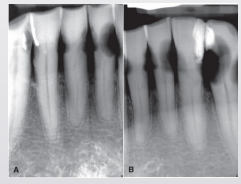

how do buccal and lingual caries show up in a radiograph

well-defined ovoid radiolucency

buccal/lingual caries may often be confused w occlusal caries due to superimposition, how can you sort of differentiate them

occlusal usually not as well-defined (pic shows B/L caries)

how can you tell solely based on the radiograph whether the pt has a buccal or lingual caries

SLOB rule!!

where do root caries typically arise

pt w gingival recession and/or bone loss, on B/L/proximal root surfaces of teeth involving cementum

shape of root caries on radiographs

saucer like irregular cavitation

root caries on radiographs can often be confused w…

cervical burnout